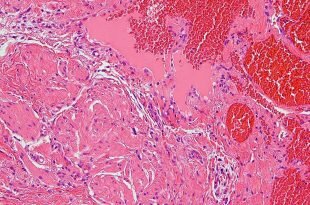

Болезни, поражающие печень, несут угрозу всему организму. Причины заболеваний железы — злоупотребление алкоголем или лекарствами, сбои в обменных процессах, инфицирование вирусами, огрехи в питании. Основные болезни — жировая дистрофия железы (гепатоз), воспаления органа различной этиологии (гепатиты), фиброзные и циррозные поражения с замещением паренхимы инертной ткань, дисфункция печени, рак. Клиника болезней скрытая, маскирующаяся под ухудшение общего состояния. Желтуха, боли справа в подреберье, тошнота говорят об усугублении процесса. В основе лечения — строгая диетотерапия, тщательный подбор гепапротекторов, отказ от вредных привычек.